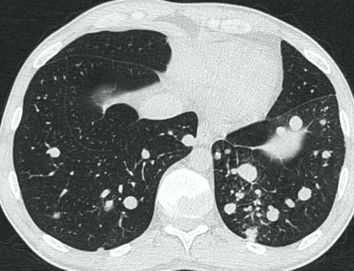

4.3. ЛУЧЕВАЯ ДИАГНОСТИКА COVID-19

Методы лучевой диагностики применяют для выявления COVID-19 пневмоний, их осложнений, дифференциальной диагностики с другими заболеваниями легких, а также для определения степени выраженности и динамики изменений, оценки эффективности проводимой терапии.

К методам лучевой диагностики патологии ОГК пациентов с предполагаемой/установленной COVID-19 пневмонией относят:

- Обзорную рентгенографию легких (РГ),

- Компьютерную томографию легких (КТ),

- Ультразвуковое исследование легких и плевральных полостей (УЗИ).

Стандартная РГ имеет низкую чувствительность в выявлении начальных изменений в первые дни заболевания и не может применяться для ранней диагностики. Информативность РГ повышается с увеличением длительности течения пневмонии. Рентгенография с использованием передвижных (палатных) аппаратов является основным методом лучевой диагностики патологии ОГК в отделениях реанимации и интенсивной терапии (ОРИТ). Применение передвижного (палатного) аппарата оправдано и для проведения обычных РГ исследований в рентгеновском кабинете. В стационарных условиях относительным преимуществом РГ в сравнении с КТ являются большая пропускная способность. Метод позволяет уверенно выявлять тяжелые формы пневмоний и отек легких различной природы, которые требуют госпитализации, в том числе направления в ОРИТ.

КТ имеет высокую чувствительность в выявлении изменений в легких, характерных для COVID-19. Применение КТ целесообразно для первичной оценки состояния ОГК у пациентов с тяжелыми прогрессирующими формами заболевания, а также для дифференциальной диагностики выявленных изменений и оценки динамики процесса. КТ позволяет выявить характерные изменения в легких у пациентов с COVID-19 еще до появления положительных лабораторных тестов на инфекцию с помощью МАНК. В то же время, КТ выявляет изменения легких у значительного числа пациентов с бессимптомной и легкой формами заболевания, которым не требуется госпитализация. Результаты КТ в этих случаях не влияют на тактику лечения и прогноз заболевания при наличии лабораторного подтверждения COVID-19. Поэтому массовое применение КТ для скрининга асимптомных и легких форм болезни не рекомендуется.